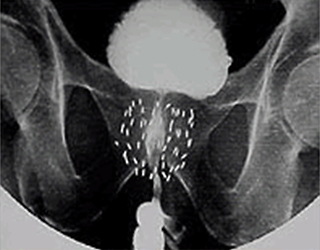

前立腺に挿入された線源のレントゲン

小さな線源を前立腺内に挿入し,前立腺内のがん病巣へ線源から放射線を照射する放射線治療です。

密封小線源療法とは何ですか?